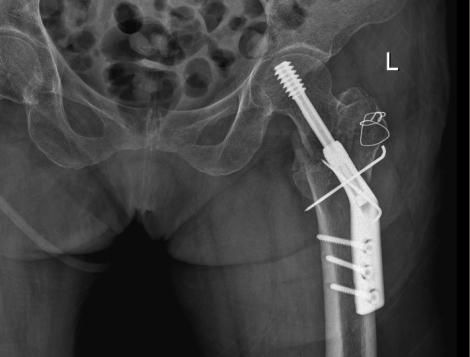

△骨科于15日、16日收治的另外兩位高齡患者

△術後